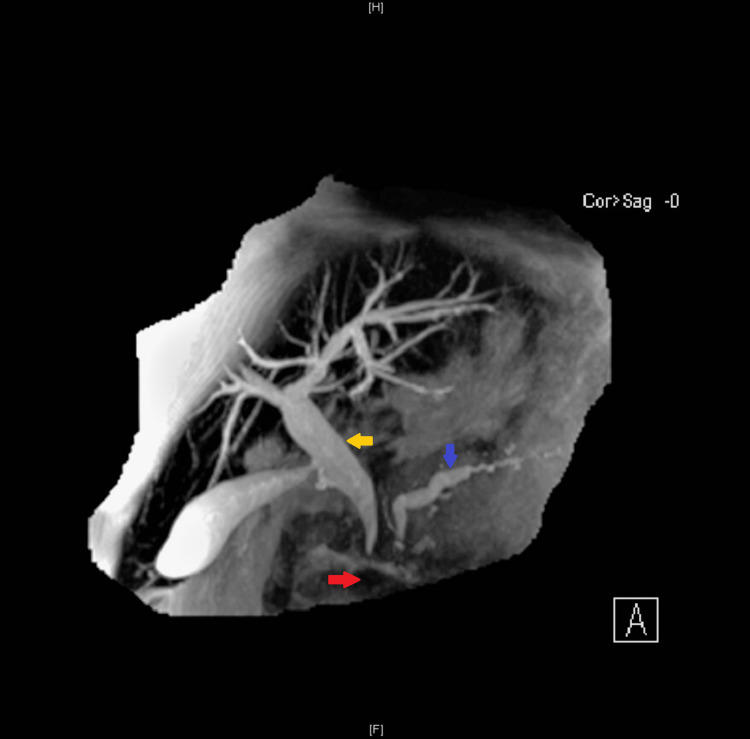

She re-presented after a couple of months with obstructive jaundice (markedly raised bilirubin and ALP). On this occasion, magnetic resonance cholangiopancreatography (MRCP) revealed dilatation of the intrahepatic biliary tree, dilatation of the CBD to 13 mm, and dilated PD up to 7 mm secondary to extrinsic obstruction at the level of the pseudocyst in the head of the pancreas (Figure 2).